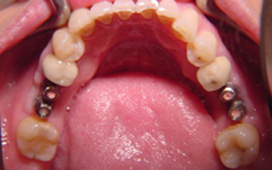

單顆雙植體 案例一